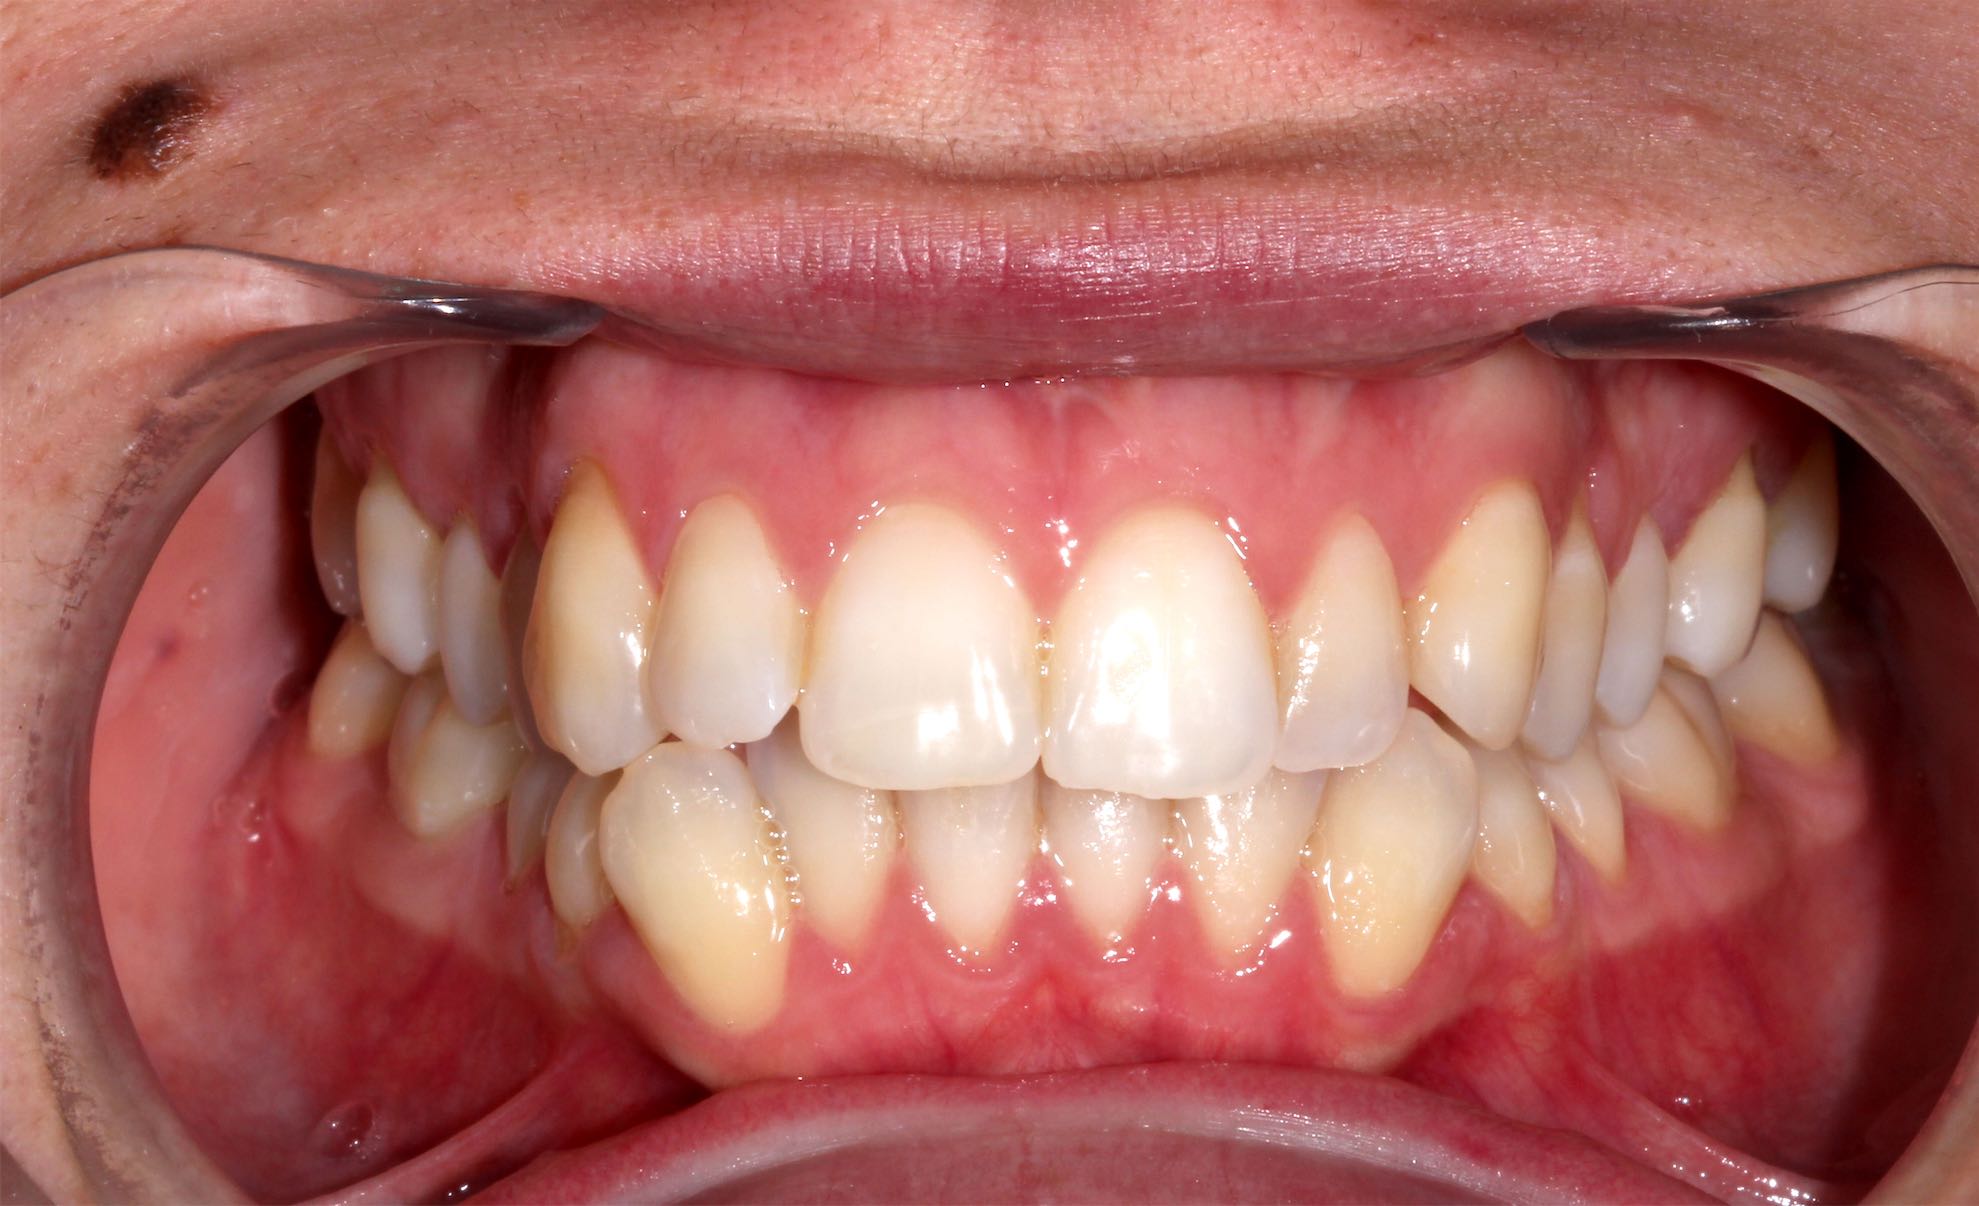

Ortodoncia

BeforeAfter